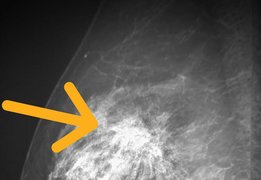

子宮頸がんは、若い女性に多く見られます。子宮の出入り口にでき、日本では毎年約1・1万人の女性が発症、毎年約2900人が亡くなっています。治療で子宮を失う人は年間で約1千人です。一生のうち、100人に1~2人が子宮頸がんにかかるとされています。

子宮頸がんは20歳代から接種、非接種の差が大きく出ます。30代、40代で罹患する人も多い。子どもがほしい、という年代で治療のために子宮を取ることもあります。ワクチンを打つメリットはあると思います。